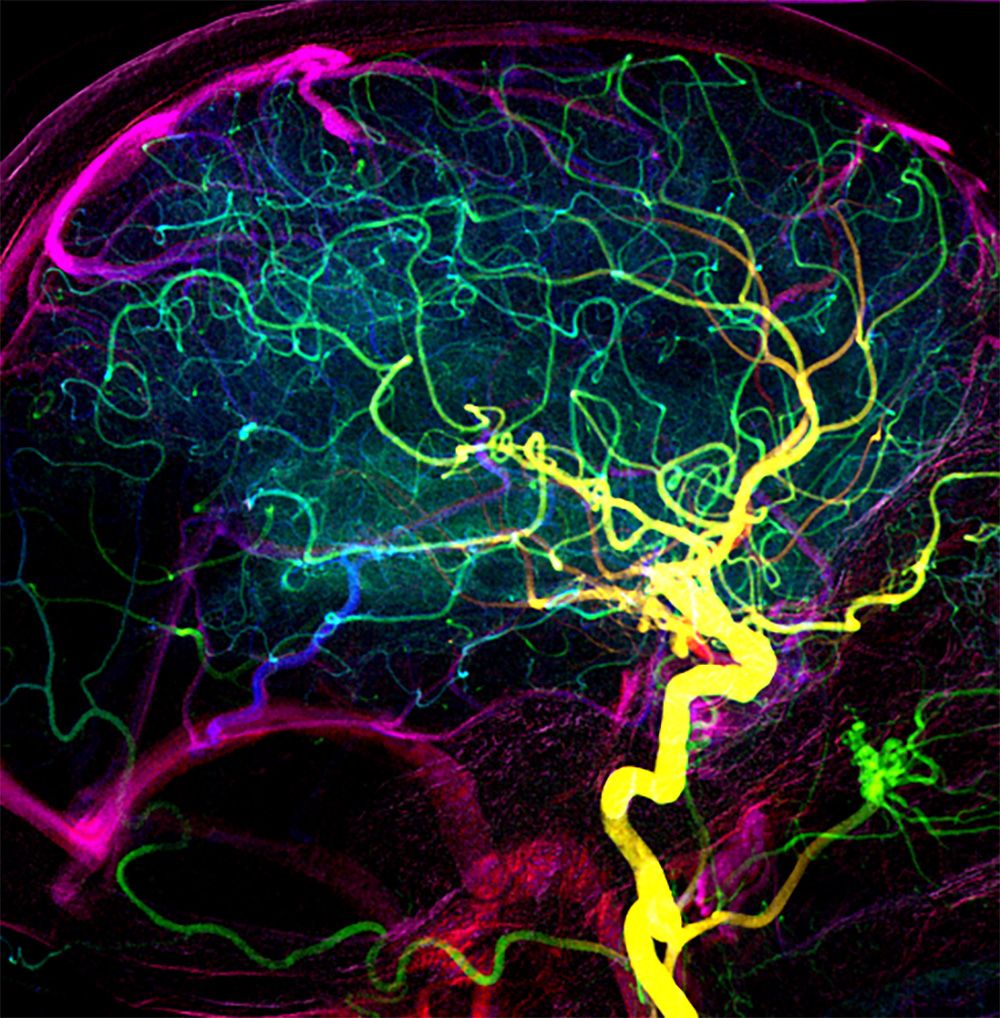

Übermässige Wiederdurchblutung im Gehirn eines Patienten mit früher venöser Füllung nach der Entfernung des Blutgerinnsels. (Bild: P. Thurner und Z. Kulcsar, USZ)

Für seine Studie setzte das Forscherteam ein Mausmodell für Schlaganfälle sowie mehrere Bildgebungsverfahren ein, um Veränderungen in der arteriellen Blutzufuhr am lebenden Organismus zu untersuchen. Bei Versuchstieren, die über schlechte Kollateralen verfügten, führte die übermässige Wiederdurchblutung nach der Entfernung des Gerinnsels zu Blutungen und einer erhöhten Sterblichkeit. Die Ergebnisse aus dem Mausmodell bestätigten sich auch in der Praxis: Patientinnen und Patienten mit schlechten Kollateralen zeigten nach erfolgter Öffnung des verstopften Blutgefässes eine ähnlich schnelle und übermässige Wiederdurchblutung des Hirnareals wie die Mäuse. Auch bei ihnen kam es zu kleinen Blutungen im Gehirn, und ihre Genesung war schlechter.